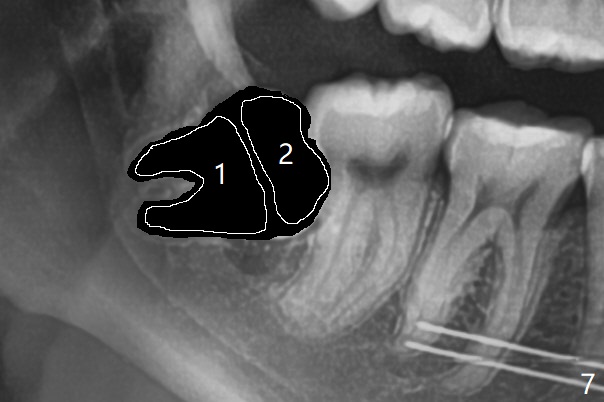

18岁女要求上大学前拔除智齿(图二),十三岁上四已经为了矫正而拔除(图一),所以现在只需要拔除下八,后者接近水平阻生,冠部可能位于下七远中颊侧(图三,四 *),所以附加切口应在七近中(红线)。智齿拔除后根部有两个牙槽窝(图五,六 *)。在右侧,塞入两个胶原塞(图七:1,2,collagen plug),其中一个末端剪开塞入根部牙槽窝。而左侧,使用一个胶原塞,但事先剪成两半(图八:1,3),第一部分也剪成燕尾,插入根部牙槽窝(1),然后在七远中放置骨水泥(1 cc Bond Apatite,2 红色),在后者上面放入胶原塞另外一半(3)。最后两侧都使用4-0 PGA 缝线。